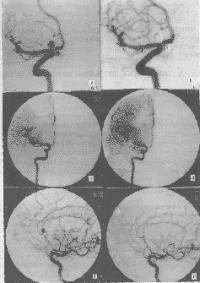

3.脑血管造影是确诊颅内动脉瘤必须的检查方法,对判明动脉瘤的准确位置、形态、内径、数目、血管痉挛和确定手术方案都十分重要。DSA更为清晰。,经股动脉插管全脑血管造影,可避免遗漏多发动脉瘤。病情在三级以下,脑血管造影应及早进行,三级和三级以上病人可待病情稳定后,再行造影检查。及早造影明确诊断,尽快手术夹闭动脉瘤,可以防止动脉瘤再次破裂出血。首次造影阴性,可能因脑血管痉挛而动脉瘤未显影,高度怀疑动脉瘤者,应在3个月后重复造影。

颅内动脉瘤多因脑动脉管壁局部的先天性缺陷和腔内压力增高的基础上引起。高血压、脑动脉硬化、血管炎与动脉瘤的发生与发展有关。脑动脉瘤多见于脑底动脉分叉之处。按其发病部位,4/5位于脑底动脉环前半,以颈内动脉、后交通动脉、前交通动脉者多见;脑底动脉环后半者约占1/5,发生于椎基底动脉、大脑后动脉及其分支。症状:动脉瘤破裂时,常有前驱症状如头痛,继之发生出血症状,表现为剧烈头痛、烦躁、恶心呕吐等脑膜刺激征,随之出现颅内压增高。可伴有意识障碍和相应部位的神经定位症状。动脉瘤出血形成较大血肿者,病情多急剧恶化,出现脑疝危象。据统计动脉瘤第一次破裂后,死亡率高达30~40%,其中半数在发病后48小时内死亡,存活的病例,1/3可发生再次出血。检查:脑血管造影是最确切的辅助诊断方法,应行全脑血管造影。CT扫描有时可以显示出动脉瘤病灶。MRI检查不仅可显示出动脉瘤,有时尚可见到附壁血栓。一旦诊断为脑动脉瘤,应采取手术治疗,以求根治,避免大出血危险。采用开颅直接处理动脉瘤的手术方法。尚可采用动脉内栓塞治疗。